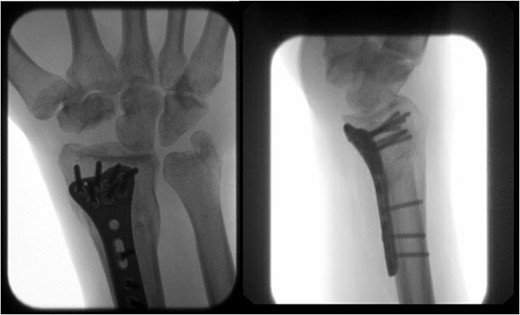

After medical optimization, the patient underwent PRC, open reduction internal fixation (ORIF) of the right distal radius fracture, and carpal tunnel release. A dorsal approach was used, with the third and fourth extensor compartments being released. At this point, extensive disruption of the dorsal wrist capsule and proximal carpal row was observed. The lunate was identified, noted to be devoid of soft tissue attachments, and was able to be excised. Completion of the PRC was achieved by excising the scaphoid and triquetrum from their minimal remaining soft tissue attachments entirely through the dorsal approach (Fig. 3). The lunate fossa of the radius, proximal capitate, and radioscaphocapitate ligament (prerequisite for successful acute PRC) was noted to be intact [2].

AP and lateral views immediately postop demonstrating right distal radius fixation and PRC.